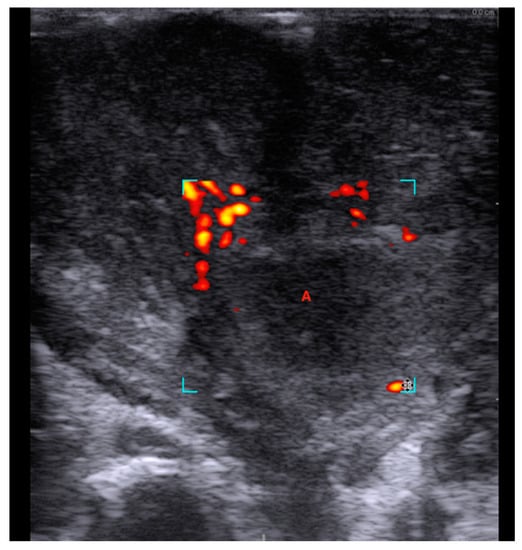

A Novel Technique for Intraoral Ultrasound-Guided Aspiration of Peritonsillar Abscess

2. Materials and Methods

3. Results